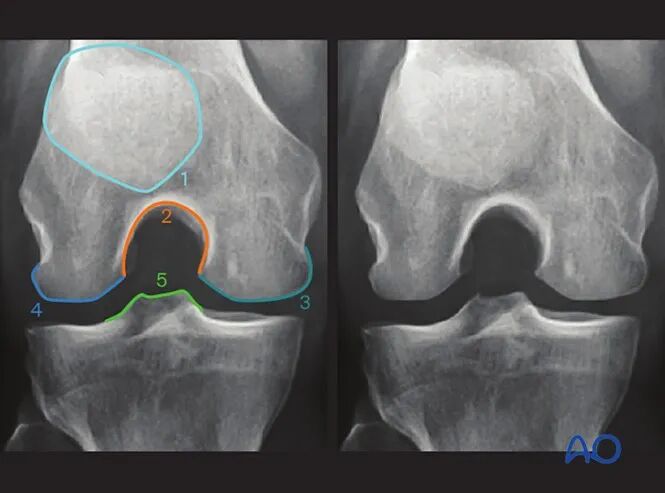

AO干货分享:

看胫骨平台是否平整的透视体位